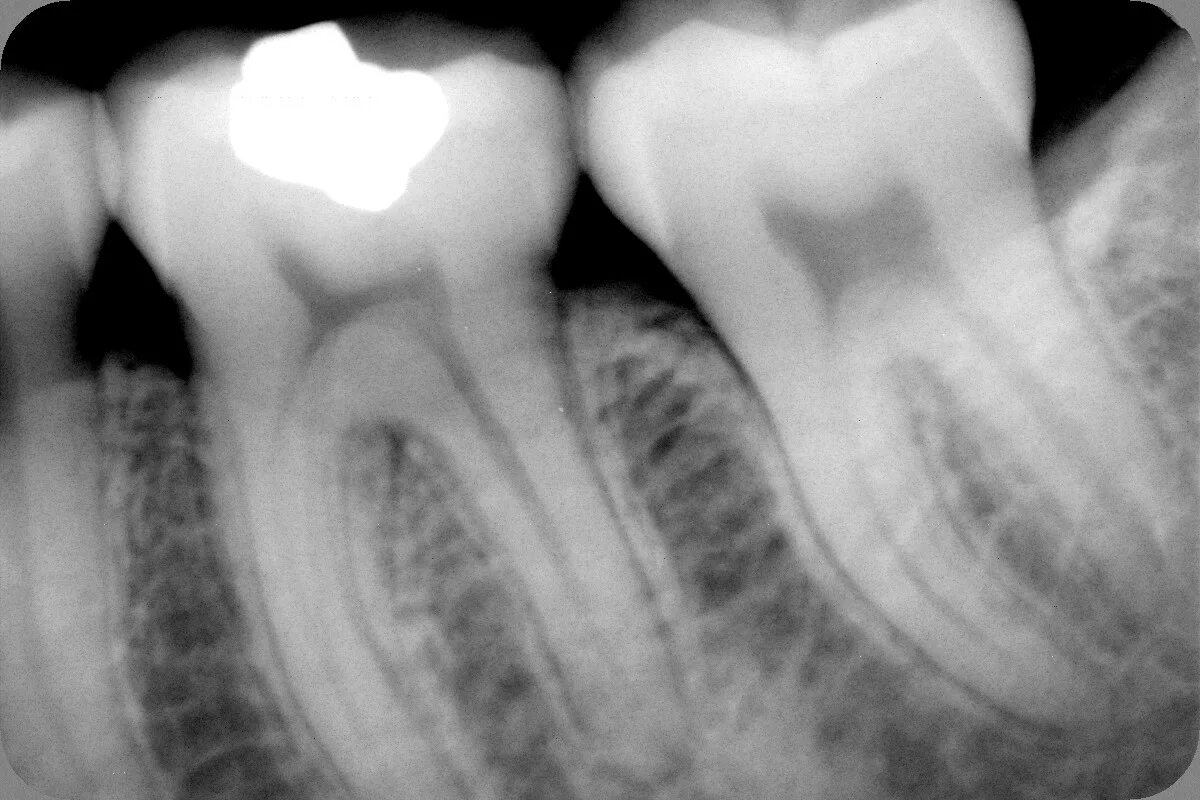

Как понять снимок зуба